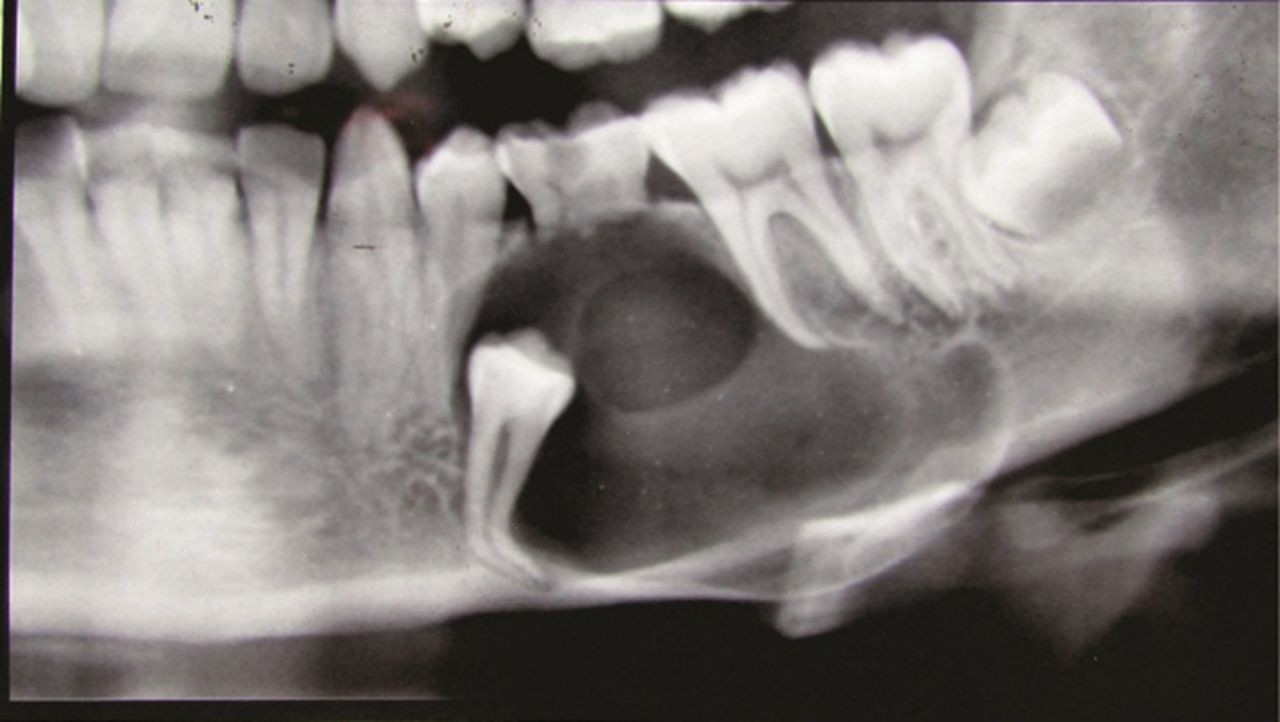

Dentigerous cyst, causes and treatment

Dentigerous cysts are the second most common type of odontogenic cyst, which is a fluid-filled sac that develops in the jaw bone and soft tissue. They form over the top of an unerupted tooth, or partially erupted tooth, usually one of your molars or canines. While dentigerous cysts are benign, they can lead to complications, such as infection, if left untreated.

How is it diagnosed?

Small dentigerous cysts often go unnoticed until you have a dental X-ray. If your dentist notices an unusual spot on your dental X-ray, they may use a CT scan or MRI scan to make sure it’s not another type of cyst, such as a periapical cyst or an aneurysmal bone cyst.

In some cases, including when the cyst is larger, your dentist may be able to diagnose a dentigerous cyst just by looking at it.